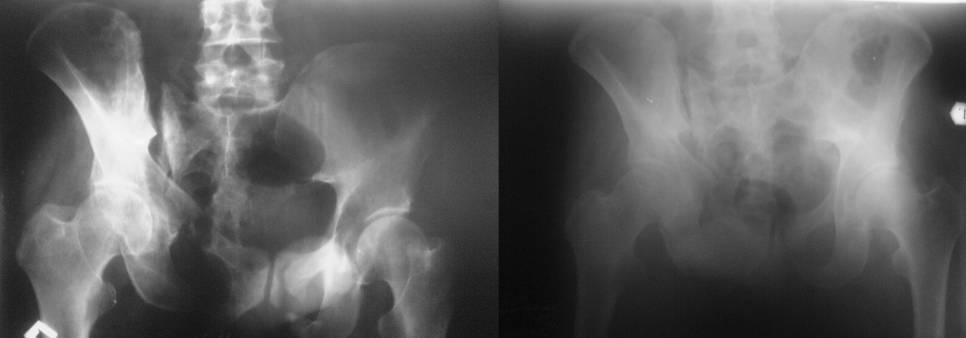

Остается только вариант закрытого аппаратного лечения. В аттаче

положение отломков на вытяжении в прямой (АР) проекции. Для сравнения

снимок до и во время вытяжения.